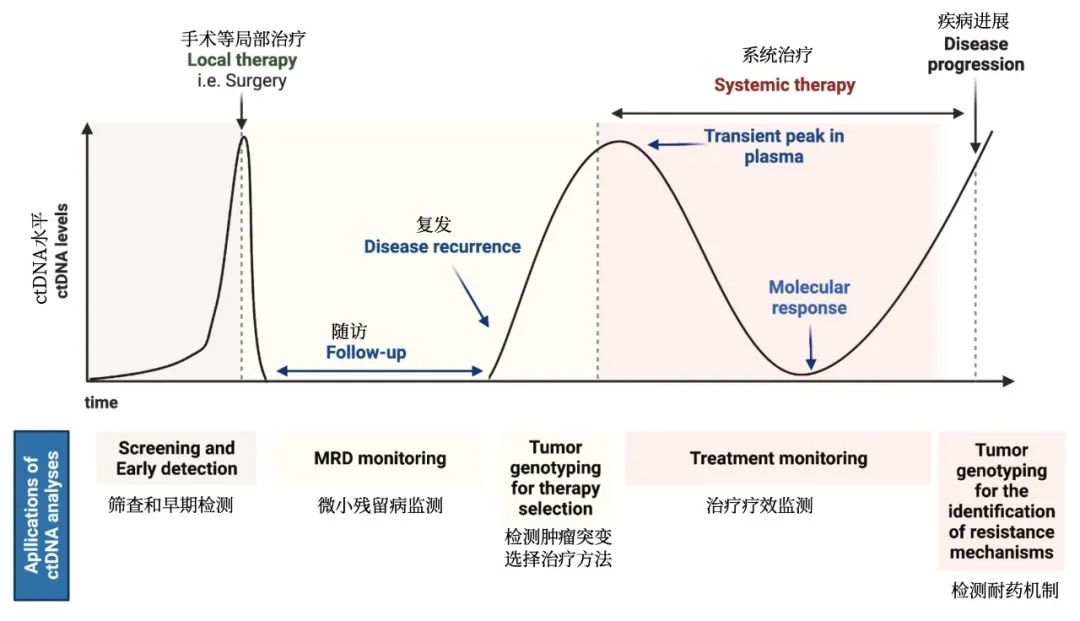

肺癌液体活检简介

肺癌液体活检简介